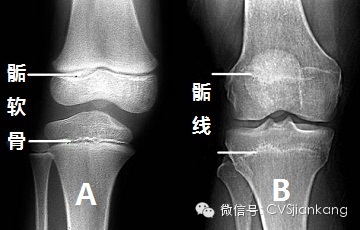

骺软骨

骺软骨(epiphysial cartilage):幼年时骺与骨干之间借透明软骨相连,该软骨称骺软骨,骺软骨细胞不断分裂、繁殖和骨化,使骨不断加长。成年后,骺软骨骨化,骨干与骺融为体,融合骺

骺软骨和骺线的名词解释骺软骨(骺板)为人体的二次骨化中心,从极端到中端共分为四个区,分别为:软骨储备区,软骨增生区,软骨钙化区和成骨区。长骨的两端膨大,称为骺。幼年